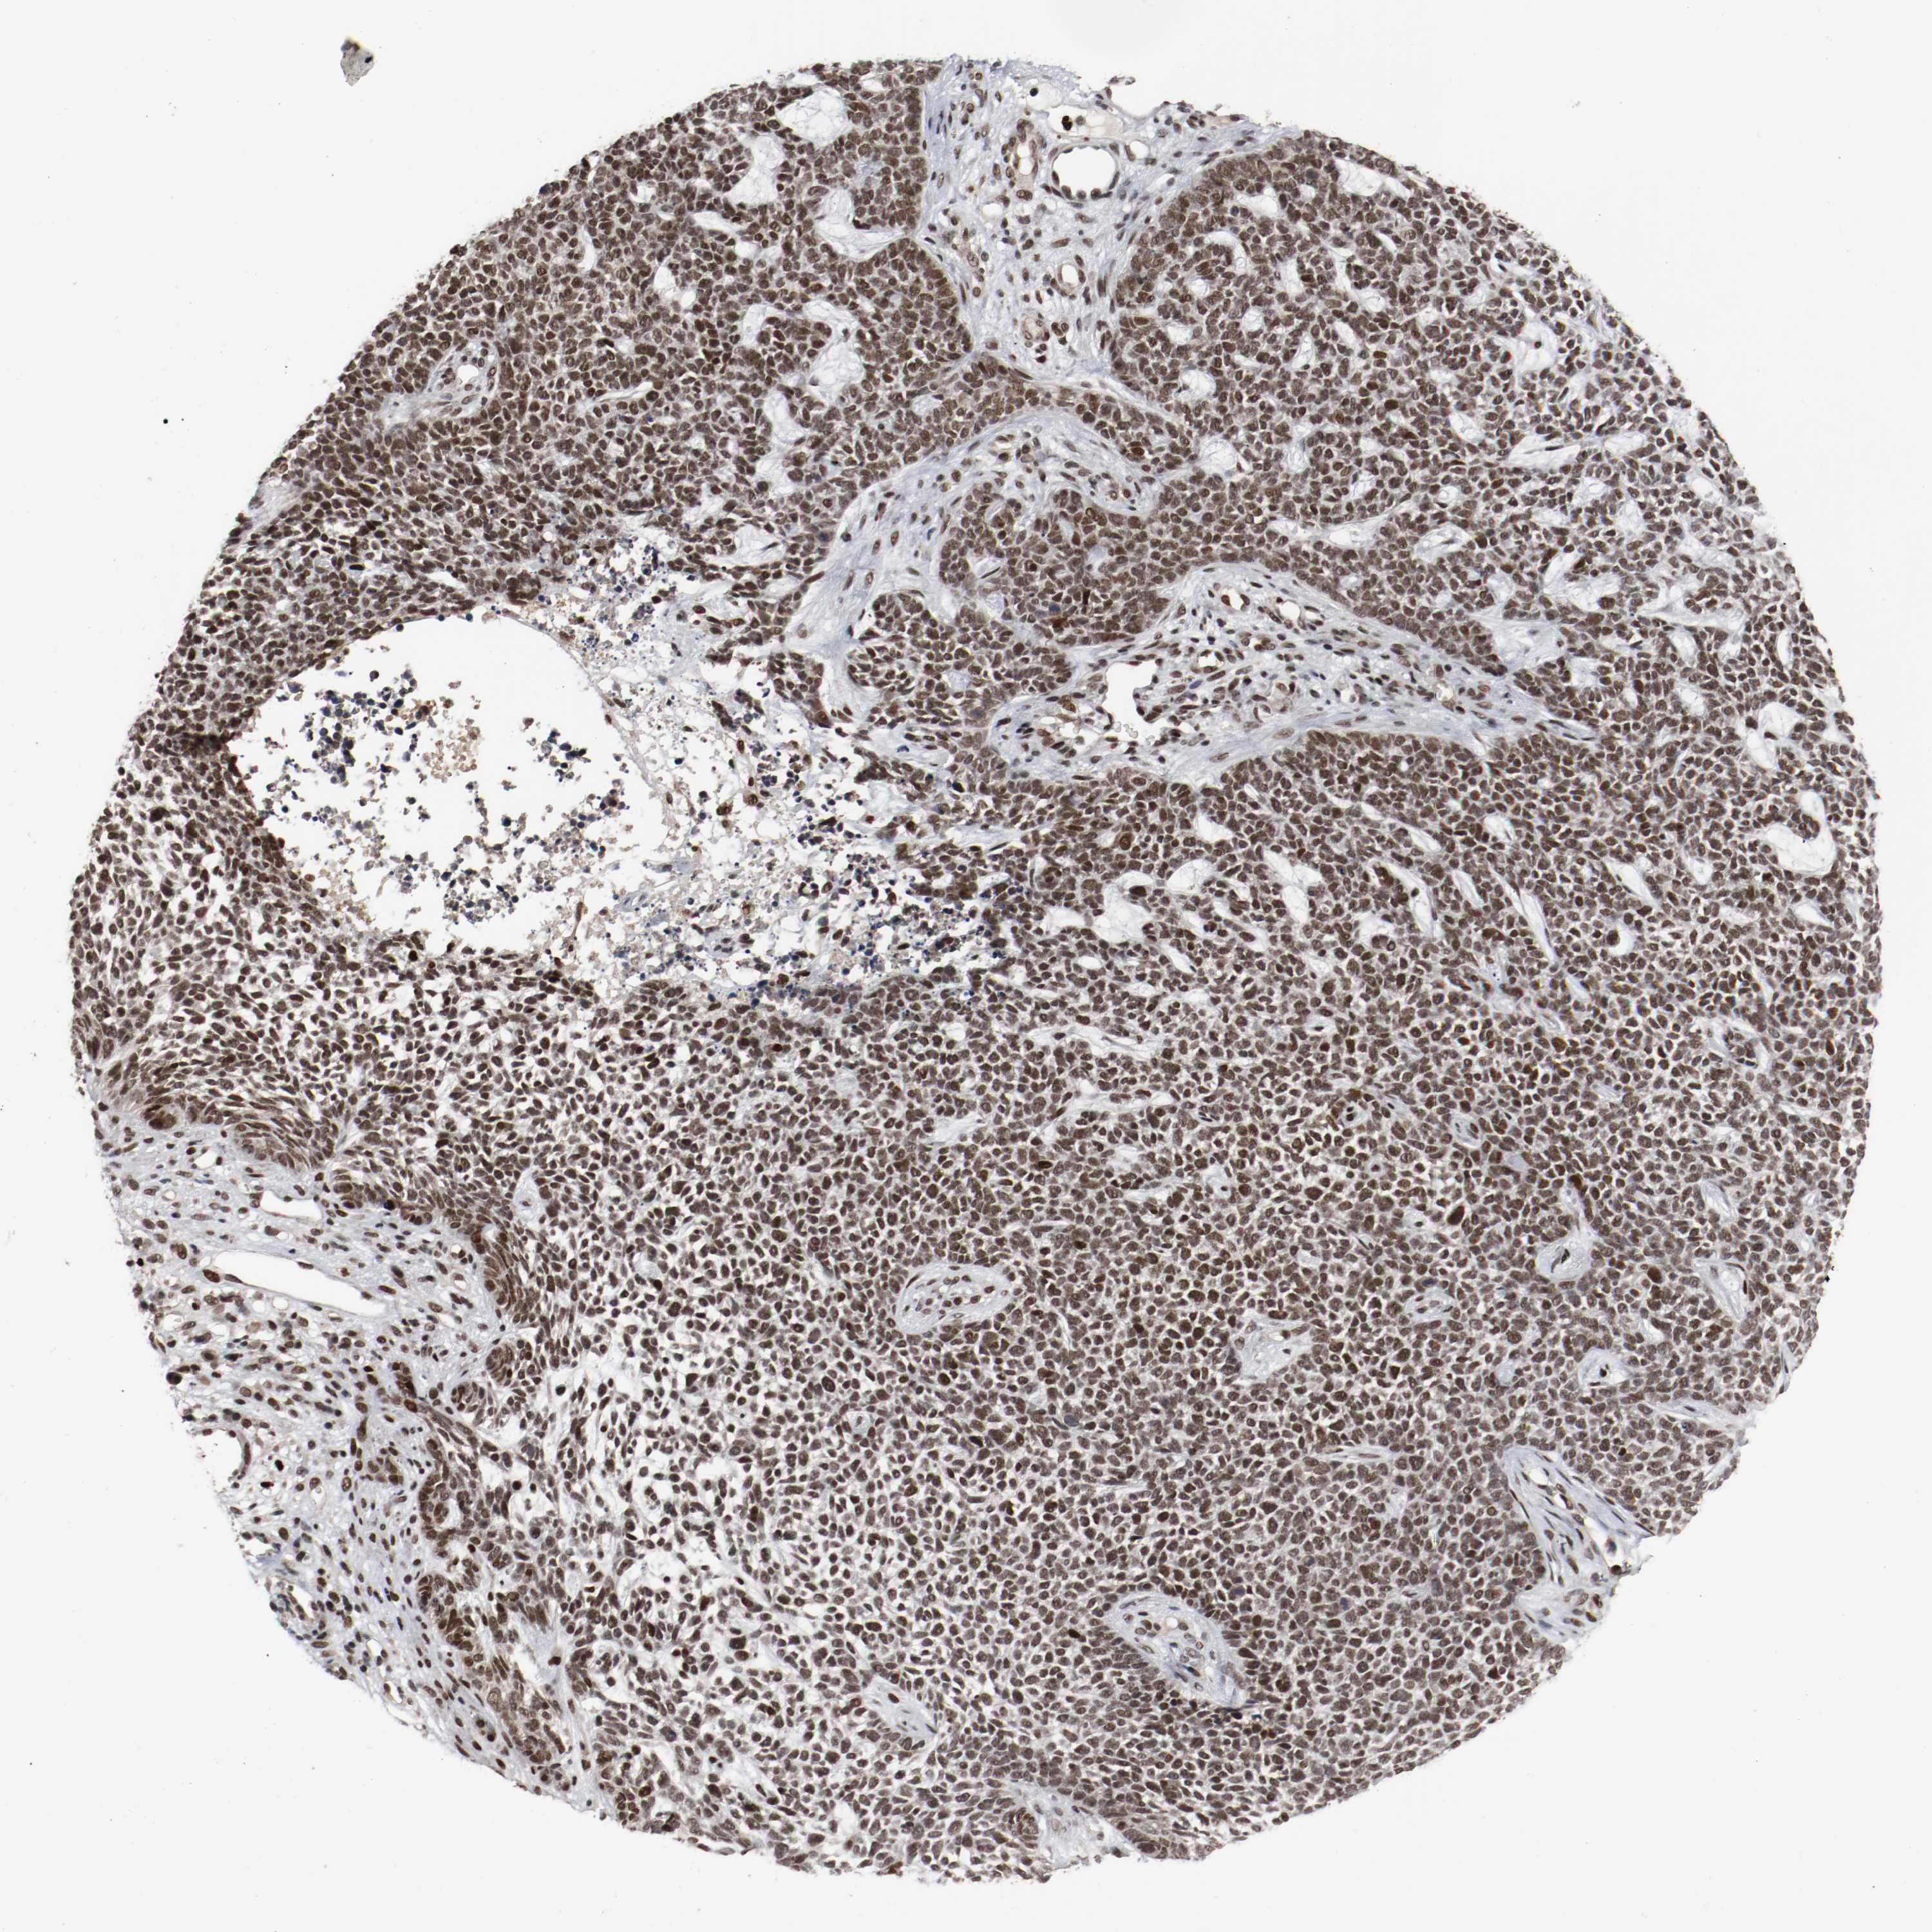

SKIN CANCER - Protein expressioni

A mouse-over function shows sample information and annotation data. Click on an image to view it in a full screen mode. Samples can be filtered based on level of antibody staining by selecting one or several of the following categories: high, medium, low and not detected. The assay and annotation is described here.

Each image is clickable and will lead to virtual microscopy that enables deeper exploration of all samples and also displays staining intensity scores, fraction scores and subcellular localization as well as patient and tissue information for each sample.

Antibody HPA004794

Staining

High

Intensity

Strong

Quantity

>75%

Location

Nuclear

Squamous cell carcinoma, NOS

Basal cell carcinoma